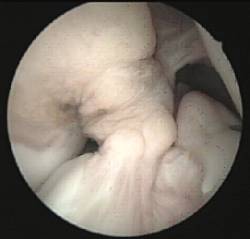

Existe asimismo la posibilidad de lesiones parciales del ligamento cruzado en las que sólo se encuentre afecto uno de los fascículos del mismo (antero medial o póstero lateral).

Cuando su afectación determina la presencia de sintomatología clínica se aconseja la reparación selectiva del fascículo lesionado mediante ligamentoplastias de refuerzo artroscópicas preservando los restos de ligamento cruzado anterior funcionantes.